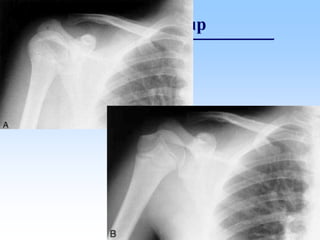

Trật khớp vai

• Trật đầu trên xương cánh tay ra trước

95%:

– Hình ảnh chỏm xương cánh tay thấp hơn ổ

chảo và di chuyển vào trong

Trật khớp vai ra trước